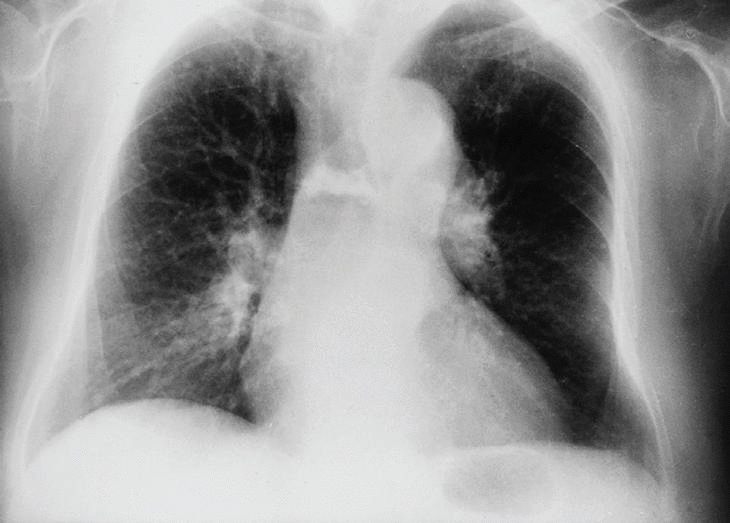

En la radiografía posteroanterior y lateral de tórax observamos como hallazgo más significativo una disminución de la altura y aumento de densidad de un cuerpo vertebral dorsal medio.

En esta paciente, coincidiendo con el dolor, se realiza radiografía dorsal donde se aprecia aplastamiento D5-D8. Posteriormente en la resonancia magnética se demuestra fractura y aplastamiento reciente de D7 en probable relación con la osteoporosis que presenta. Se le realizó una vertebroplastia mejorando clínicamente en el plazo de varios días.